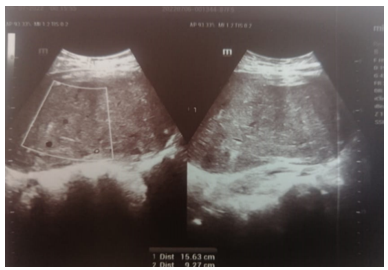

Pelvic ultrasound showed the presence of a bully uterine tissue mass, roughly oval, with lobulated contours, discreetly vascularized on color Doppler measuring 15x9cm.

Abdomino-pelvic CT objectified the presence of an intra-uterine tissue mass lateralized on the left heterogeneously enhanced after injection of PDC, fairly well limited, seat of the area of necrosis, measuring 127x80x165cm. Associated with left external iliac adenopathy of 8 mm Probably related to uterine myoma.

Fig 2: Echographic aspect tissue mass of heterogeneous uterine origin measuring 15 cm

Fig 3: CT appearance of a tissue mass of hetero-dense uterine origin poorly limited in places measuring 15 cm